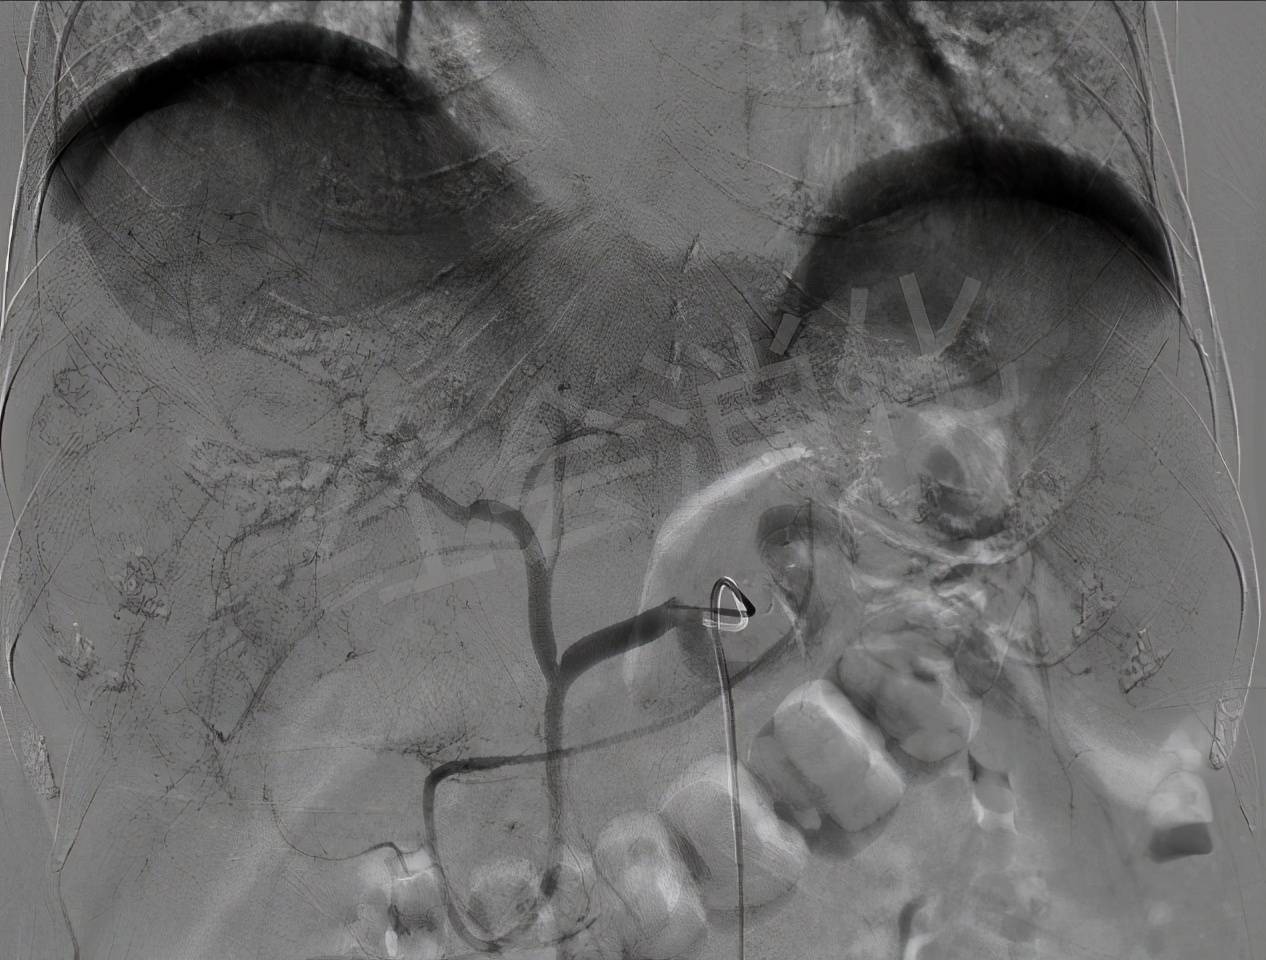

腹主动脉造影 , 明确肝动脉位置

文章图片